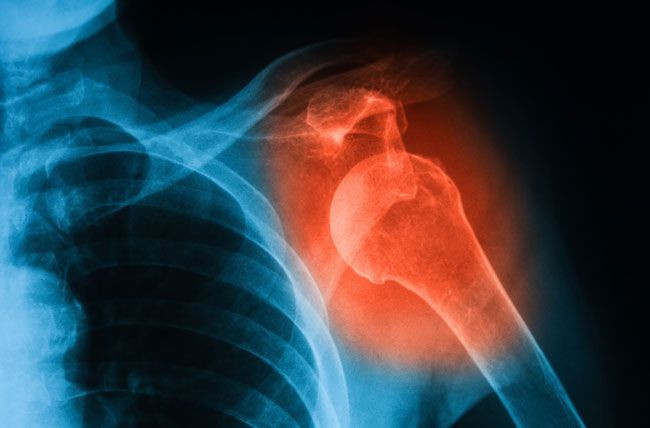

Dislokasi tulang adalah istilah medis untuk tulang di salah satu persendian Anda yang terlempar atau terdorong keluar dari tempat seharusnya.

Setiap sendi di tubuh Anda bisa terkilir. Dislokasi tulang bisa menyakitkan dan menyulitkan (atau tidak mungkin) menggunakan sendi yang terkena. Dislokasi juga dapat meregangkan atau merobek jaringan di sekitar persendian Anda, termasuk: otot, saraf, tendon dan pembuluh darah.

Dislokasi sangat umum. Sendi yang paling sering mengalami dislokasi meliputi: jari, bahu, lutut, siku, panggul, hingga mulut.